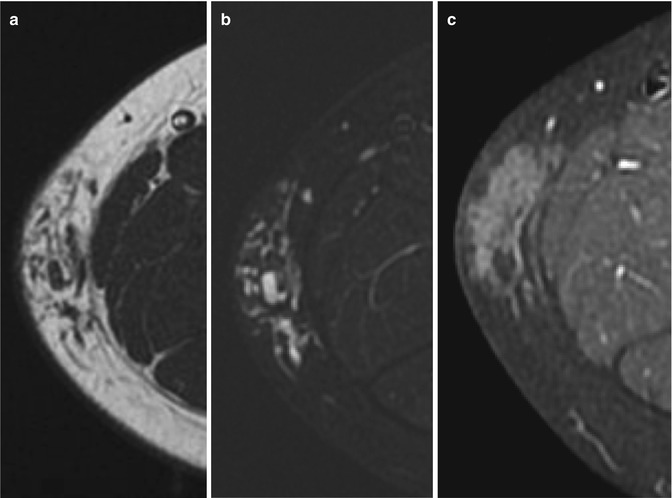

Infantile haemangioma of the cheek in a 7-year-old girl during involution phase. (a) Axial T1-weighted MR image. (b) Axial T2-weighted MR image with fat suppression. (c) Axial T1-weighted MR image after Gadolinium contrast administration with fat suppression. MRI images show a subcutaneous hyperintense mass on T1-weighted image (a), slightly hyperintense on T2-weighted image (b) with minimal enhancement (c). No flow voids are seen